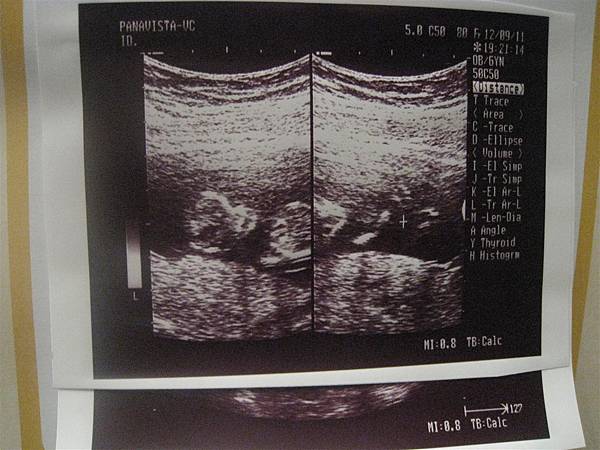

100.12.09 看到小小寶寶的樣子了,手腳都很清楚,

還不知道是男孩還是女孩,

不過,健康就好,男孩女孩都會是我們的心肝寶貝的。